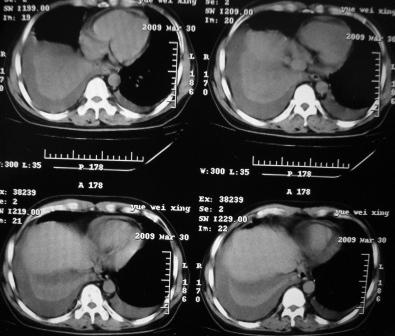

xx 男 43岁

右肺下叶支气管中断闭塞,右下肺见不规块影,并胸腔积液,考虑肺中央型肺癌继发下叶不张,\\双侧胸腔积液,心包积液。

1)考虑右侧中央型肺癌伴右肺下叶不张,双肺及纵隔淋巴转移。2)双侧胸腔积液,以右侧为甚。3)心包积液。

1.两肺继发型tb。

2.右侧中央型肺癌并双肺及纵隔淋巴转移,心包积液,双侧胸腔积液伴右肺下叶肺不张。

考虑右肺下叶中心性肺癌并纵隔淋巴结、双肺转移伴右肺下叶阻塞性肺不张;双侧胸水,右侧为著;心包积液